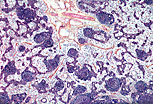

卵巢皮质位于卵巢外周,由纯细胞性结缔组织构成,其中包含圆形的卵巢卵泡,这些卵泡的大小随其发育和退化过程发生变化。 |